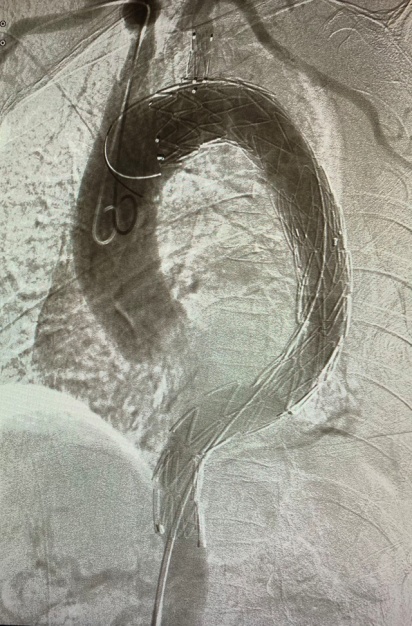

主动脉覆膜支架腔内置入术是目前主动脉夹层(Debakey Ⅲ型)治疗的首选手段,较之传统的外科开胸手术治疗,主动脉覆膜支架腔内置入术具有微创(仅需外周动脉穿刺)、术时短、成功率高、病死率低和并发症低等优点。